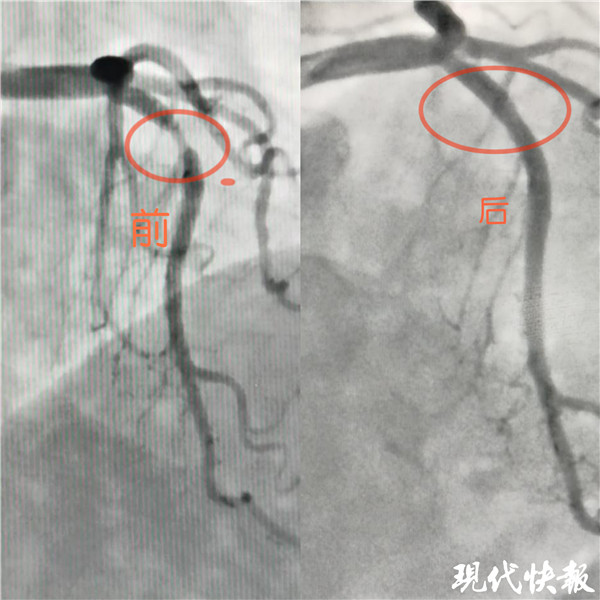

記者了解到,入院后完善冠狀動脈造影檢查示,張女士LM正常,LAD近段血管90%狹窄, LCX及RCA未見狹窄?;窗彩幸辉盒膬瓤平槿胫委焾F隊嚴格把握適應癥,和患者及家屬溝通后,于LAD病變處植入一枚藥物可吸收支架,術后血管內超聲檢查提示支架貼壁良好。